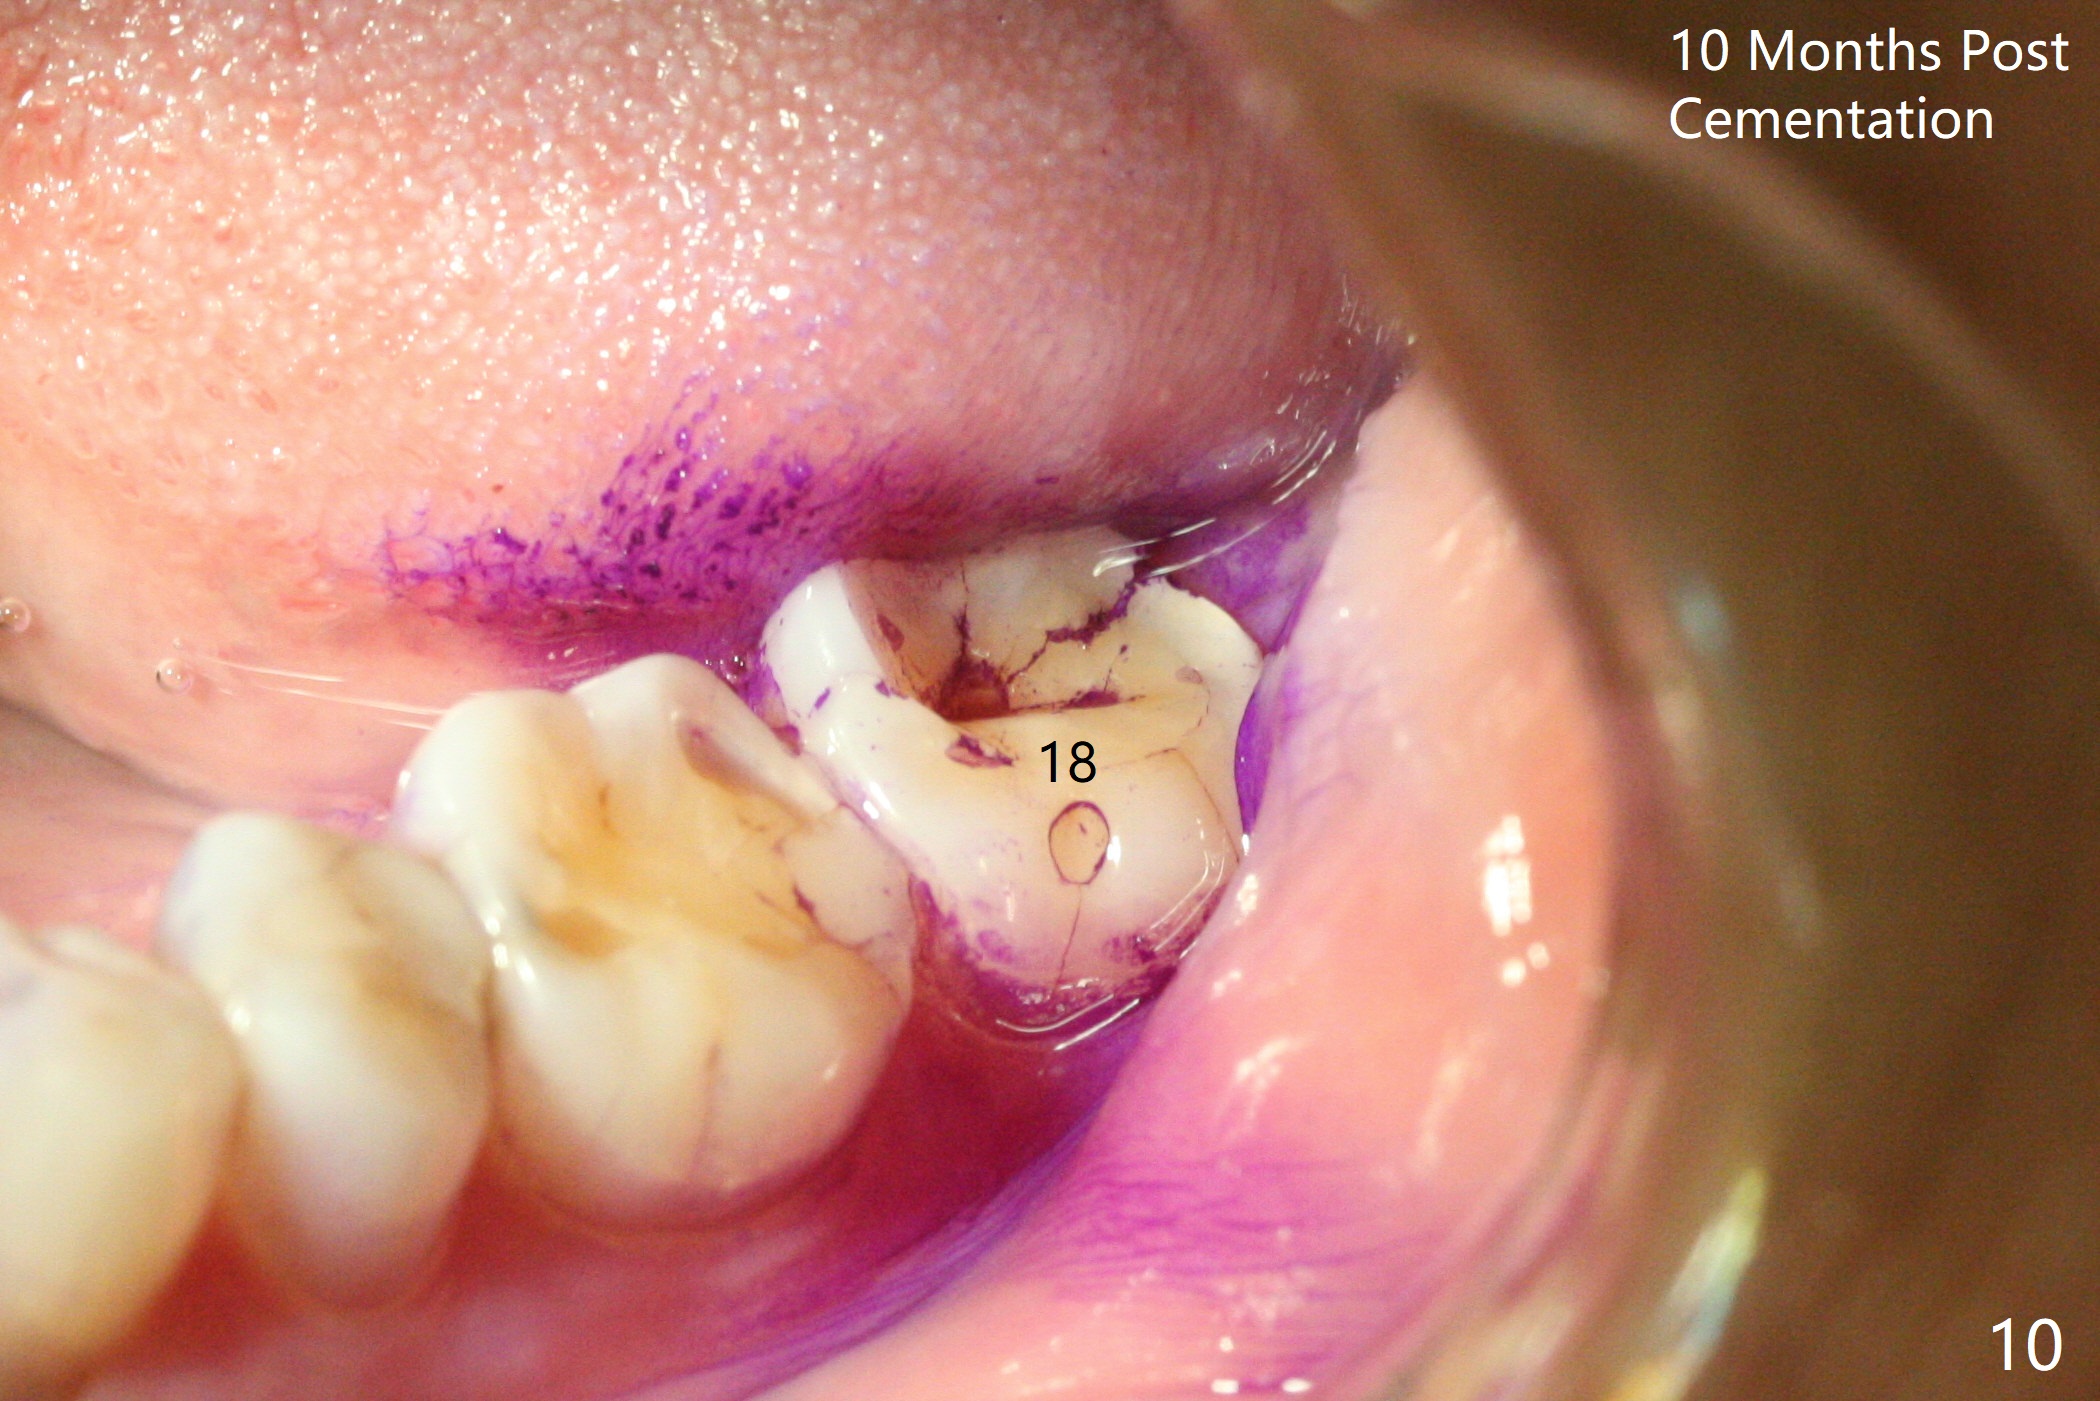

The ridge is wide at #14 11 months post socket preservation. Access and bone expansion (BEB) starts with Magic Split, followed by Magic Expanders 3.0, 3.8 and 4.3 mm from 8 to 9 mm for sinus lift. No bone is removed for osteotomy. Instead bone condensation occurs. After placement of a 4.5x11 mm dummy FC implant (Fig.1 with sinus lift (without bone graft)), a 5x9(2) mm Magicore (2 mm cuff) is placed with >55 Ncm with cuff margin at the gingival margin (Fig.2); a 5.5x3 mm solid abutment tries in. There is no occlusal clearance; trimming of the solid abutment will be needed. Later a healing screw is placed (Fig.3 *). There is no bone loss 5.5 months postop (Fig.4). A healing cap is placed without much tissue blanching. Instead a 5.5x3 mm solid abutment is placed; after height adjustment, impression is taken. A permanent crown is temporarily cemented 6 months postop (to rule out food impaction) and permanently re-cemented 7 months postop (Fig.5,6). CBCT taken 3-4 months post cementation shows that the implant threads are within the bone (Fig.7) and that the implant barely enters the sinus (Fig.8 *). That is significant since the patient has chronic sinusitis with thickened sinus membrane (Fig.9 *). The tooth #18 seems to have crazing line 10 months post cementation of the crown at #14 (overloading, Fig.10).